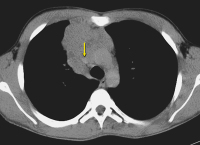

Thoraxröntgen

Abbildung 1: Thoraxröntgen eines 18-jährigen Patienten mit mediastinaler Verschattung.